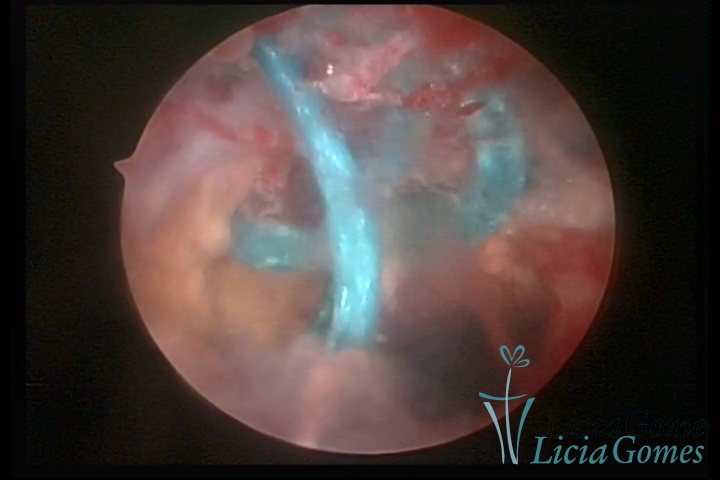

Cesarean section scar with a non-absorbed suture, as a foreign body

×